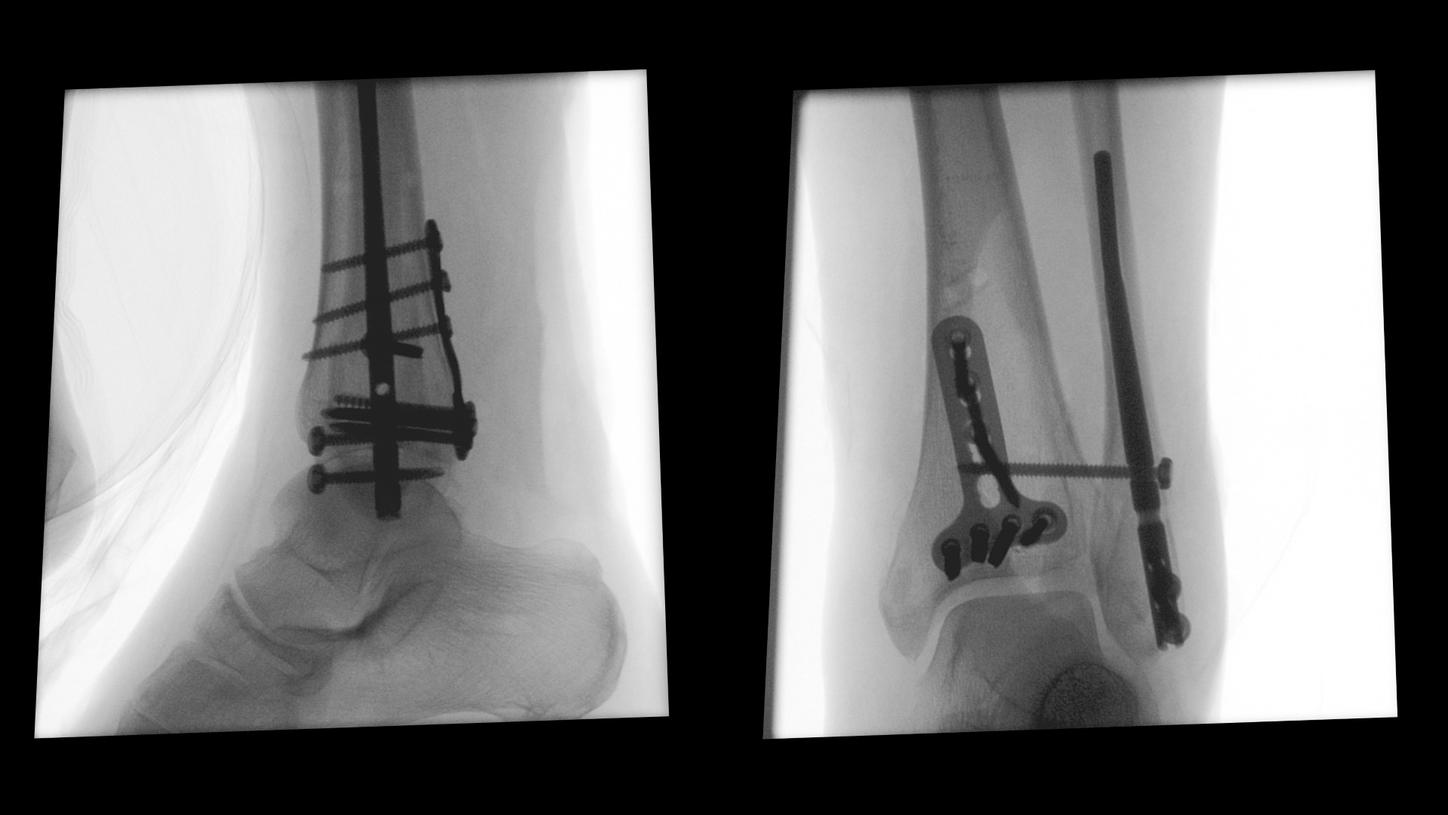

CIARTIC Move already has proven its benefits in a preclinical study1: The system enabled significant time savings for all three anatomical regions included in the study (pelvis, spine, distal radius).

Benefit from precise 2D and 3D visualization of anatomical structures and metallic objects with excellent image quality.